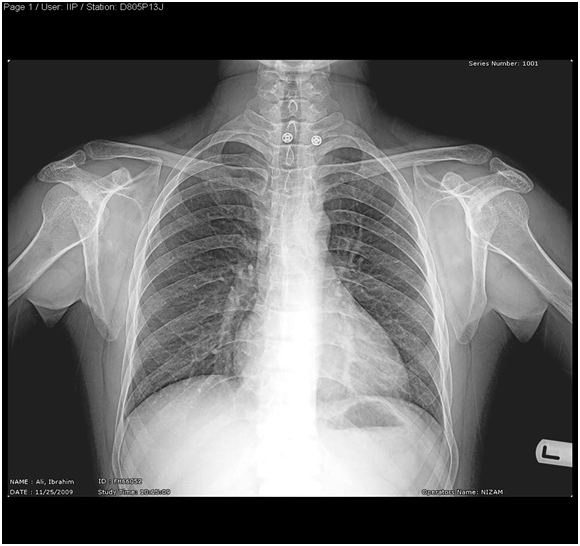

- Muscles bulk is Normal! but shoulder & pelvic girdles are weak; Proximal Myopathy

- No skeletal abnormality, no masses…

- No specific Neurologic deficit detected!

- Difficulty in standing without support with unsteadiness in walking